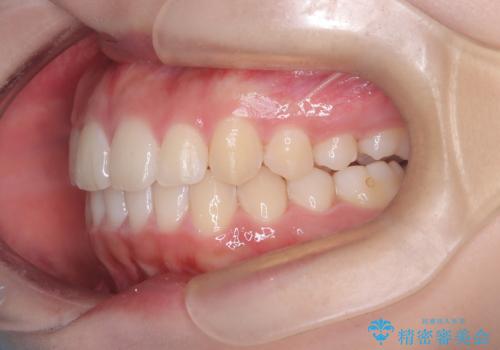

- 患者様は、**下の前歯のがたつき(叢生)**を気にされて来院されました。

下の前歯のがたつきは解消され、滑らかなアーチ状の歯並びとなりました。